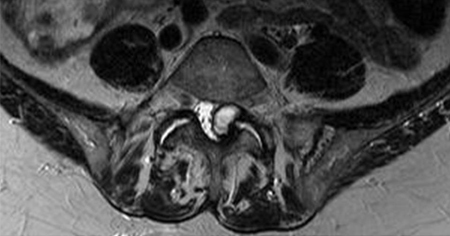

- MRI spine